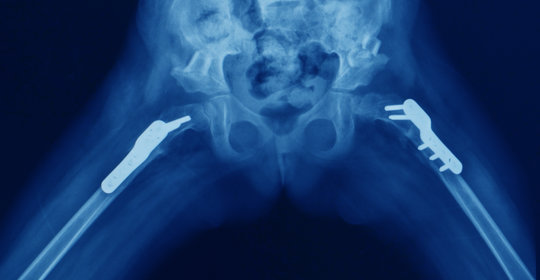

先天性恥骨聯合不連線的檢查

先天性恥骨聯合不連線的治療方案需個體化制定。輕度病例可採用彈性繃帶固定或支具外固定,以穩定關節;重度者則需要手術干預。

嚴重畸形或伴有功能障礙時,開放復位內固定術是常用的治療方法之一,旨在恢復骨骼結構和功能。手術具體方式取決於病情復雜程度,在有經驗的外科醫師操作下完成。術後注意休息與患處保護,避免劇烈運動以免影響傷口癒合。